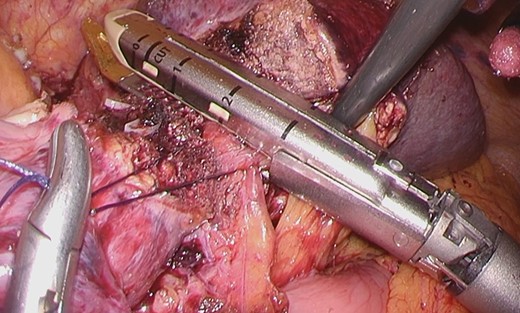

Considering the small remnant right lobe and abnormal ICG15, we planned to perform laparoscopic anatomical S3 segmentectomy. The procedures were performed using a pressure-controlled carbon dioxide pneumoperitoneum, which was maintained below 12 mmHg. Intraoperative findings showed hypoplasia of the right hepatic lobe and hypertrophy of the left hepatic lobe (Fig. 2). Intraoperative ultrasound (IOUS) was performed to confirm the location of the tumor and its relationship to the adjacent structures. The Glissonian pedicle to S3 was isolated with meticulous dissection and was then transected using the SigniaTM Stapling System and Endo GIATM Curved Tip Reload with Tri-StapleTM Technology 30 mm, Vascular Medium (Covidien, USA) (Fig. 3). The ischemic margin of S3 was marked using electrocautery (Fig. 4). Using the crush-clamp method with a harmonic scalpel (Ethicon, USA), the liver parenchyma was transected along the left hepatic vein (Fig. 5). Pringle’s maneuver was performed by clamping the hepatoduodenal ligament using the tourniquet method for 15 min with following a 5-min release period, and a total of fourteen temporary clamps were performed during parenchymal resection. The resected specimens were removed in a retrieval bag through an umbilical port site. The resected specimen showed a 41-mm simple nodular type of HCC and a 5-mm tumor-free resection margin (Fig. 6). Each port was placed as shown in Fig. 7.

The Glissonian pedicle to S3 was transected using the SigniaTM Stapling System.